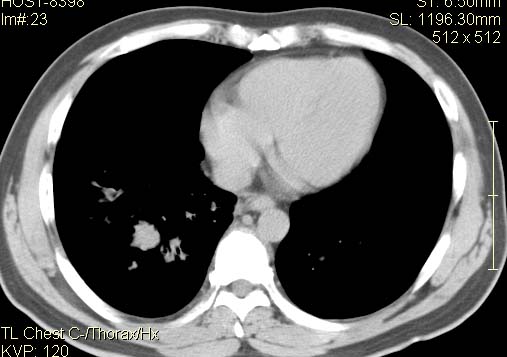

以下是引用qc80012345在2007-4-17 12:33:00的发言:[br]右肺下叶周围型肺癌伴肺门及纵隔内淋巴结转移;比较清楚。

以下是引用qingyuan在2007-4-17 14:19:00的发言:[br]右肺下叶外侧后段胸膜下区节结样病变、分叶、内可见空洞,壁厚薄不均,胸膜凹陷、肺门周围区纹理增粗、僵硬、并近似小结节样改变,肺门区软组织节结、纵膈淋巴结肿大,患者病史长、抗炎治疗无好转炎性改变基本排除,考虑:右肺下叶周围型肺癌伴纵膈及右肺门区淋巴结转移、肺内淋巴管受侵。